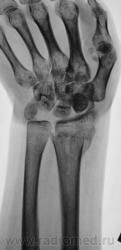

Травма.   Пациент направлен на рентгенографию лучезапястного сустава.

Вывих трапеции и гороховидной костей, ну и перелом "луча" в т.м., куда же без него.